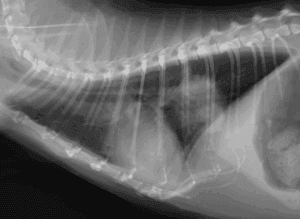

犬の小腸腺癌

犬の小腸腺癌は小腸粘膜上皮由来の悪性上皮性腫瘍で、消化器型リンパ腫に次いで2番目に発生が多い消化管腫瘍です。発生頻度は高くありませんが、局所浸潤性が強く、進行に伴いリンパ節や腹腔内臓器へ転移する可能性があります。腫瘍が発 […]